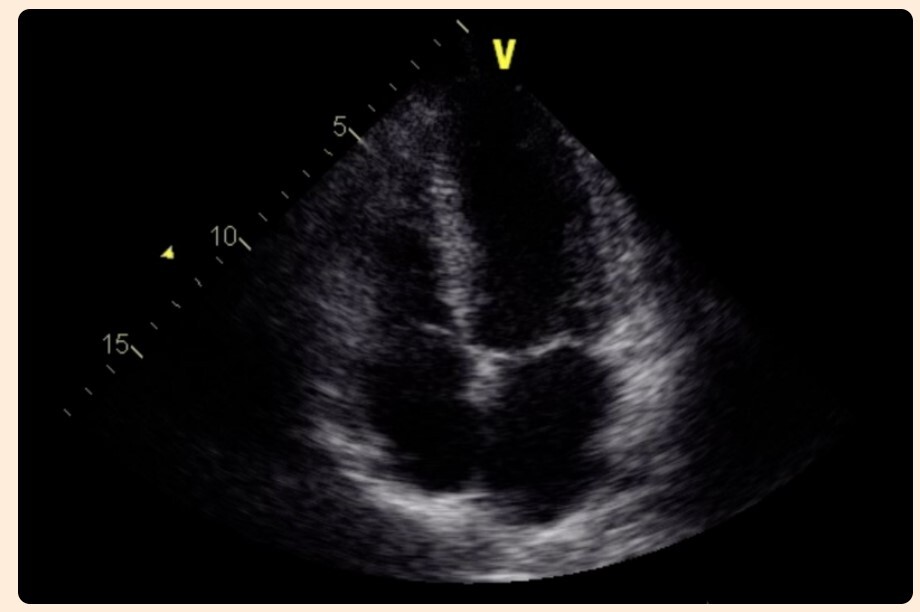

Parasternal long axis view - 3rd-5th interspace, just to the left of the sternum, probe indicator toward the right shoulder. RV, LV, LA, LVOT with aortic and mitral valves. Turn on doppler to evaluate for aortic regurgitation.